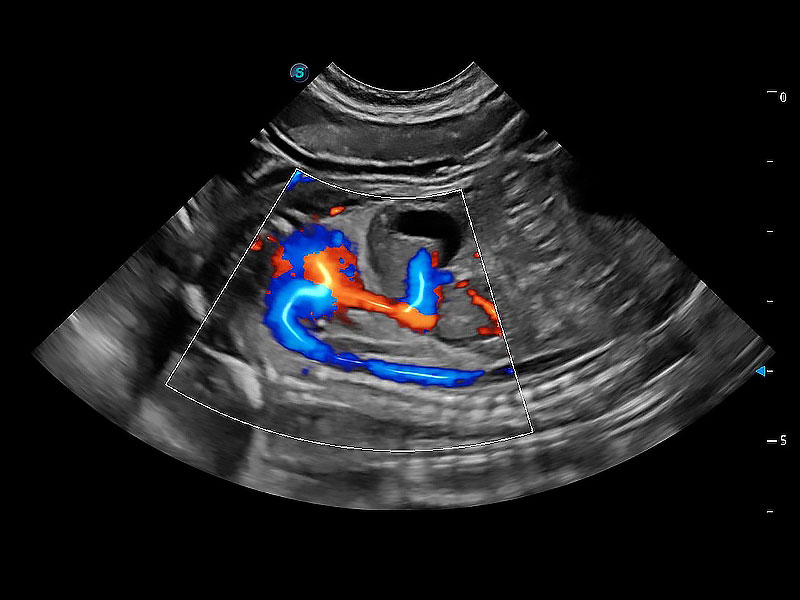

• Bright Flow 立体血流成像

在传统二维血流成像的基础上,呈现血流的立体感,具有动感的生命力之美。即便是微小的血管也能轻松应对,提高了血流的视觉敏感性。

(犬)胎儿主动脉弓立体血流

(犬)二腔心血流